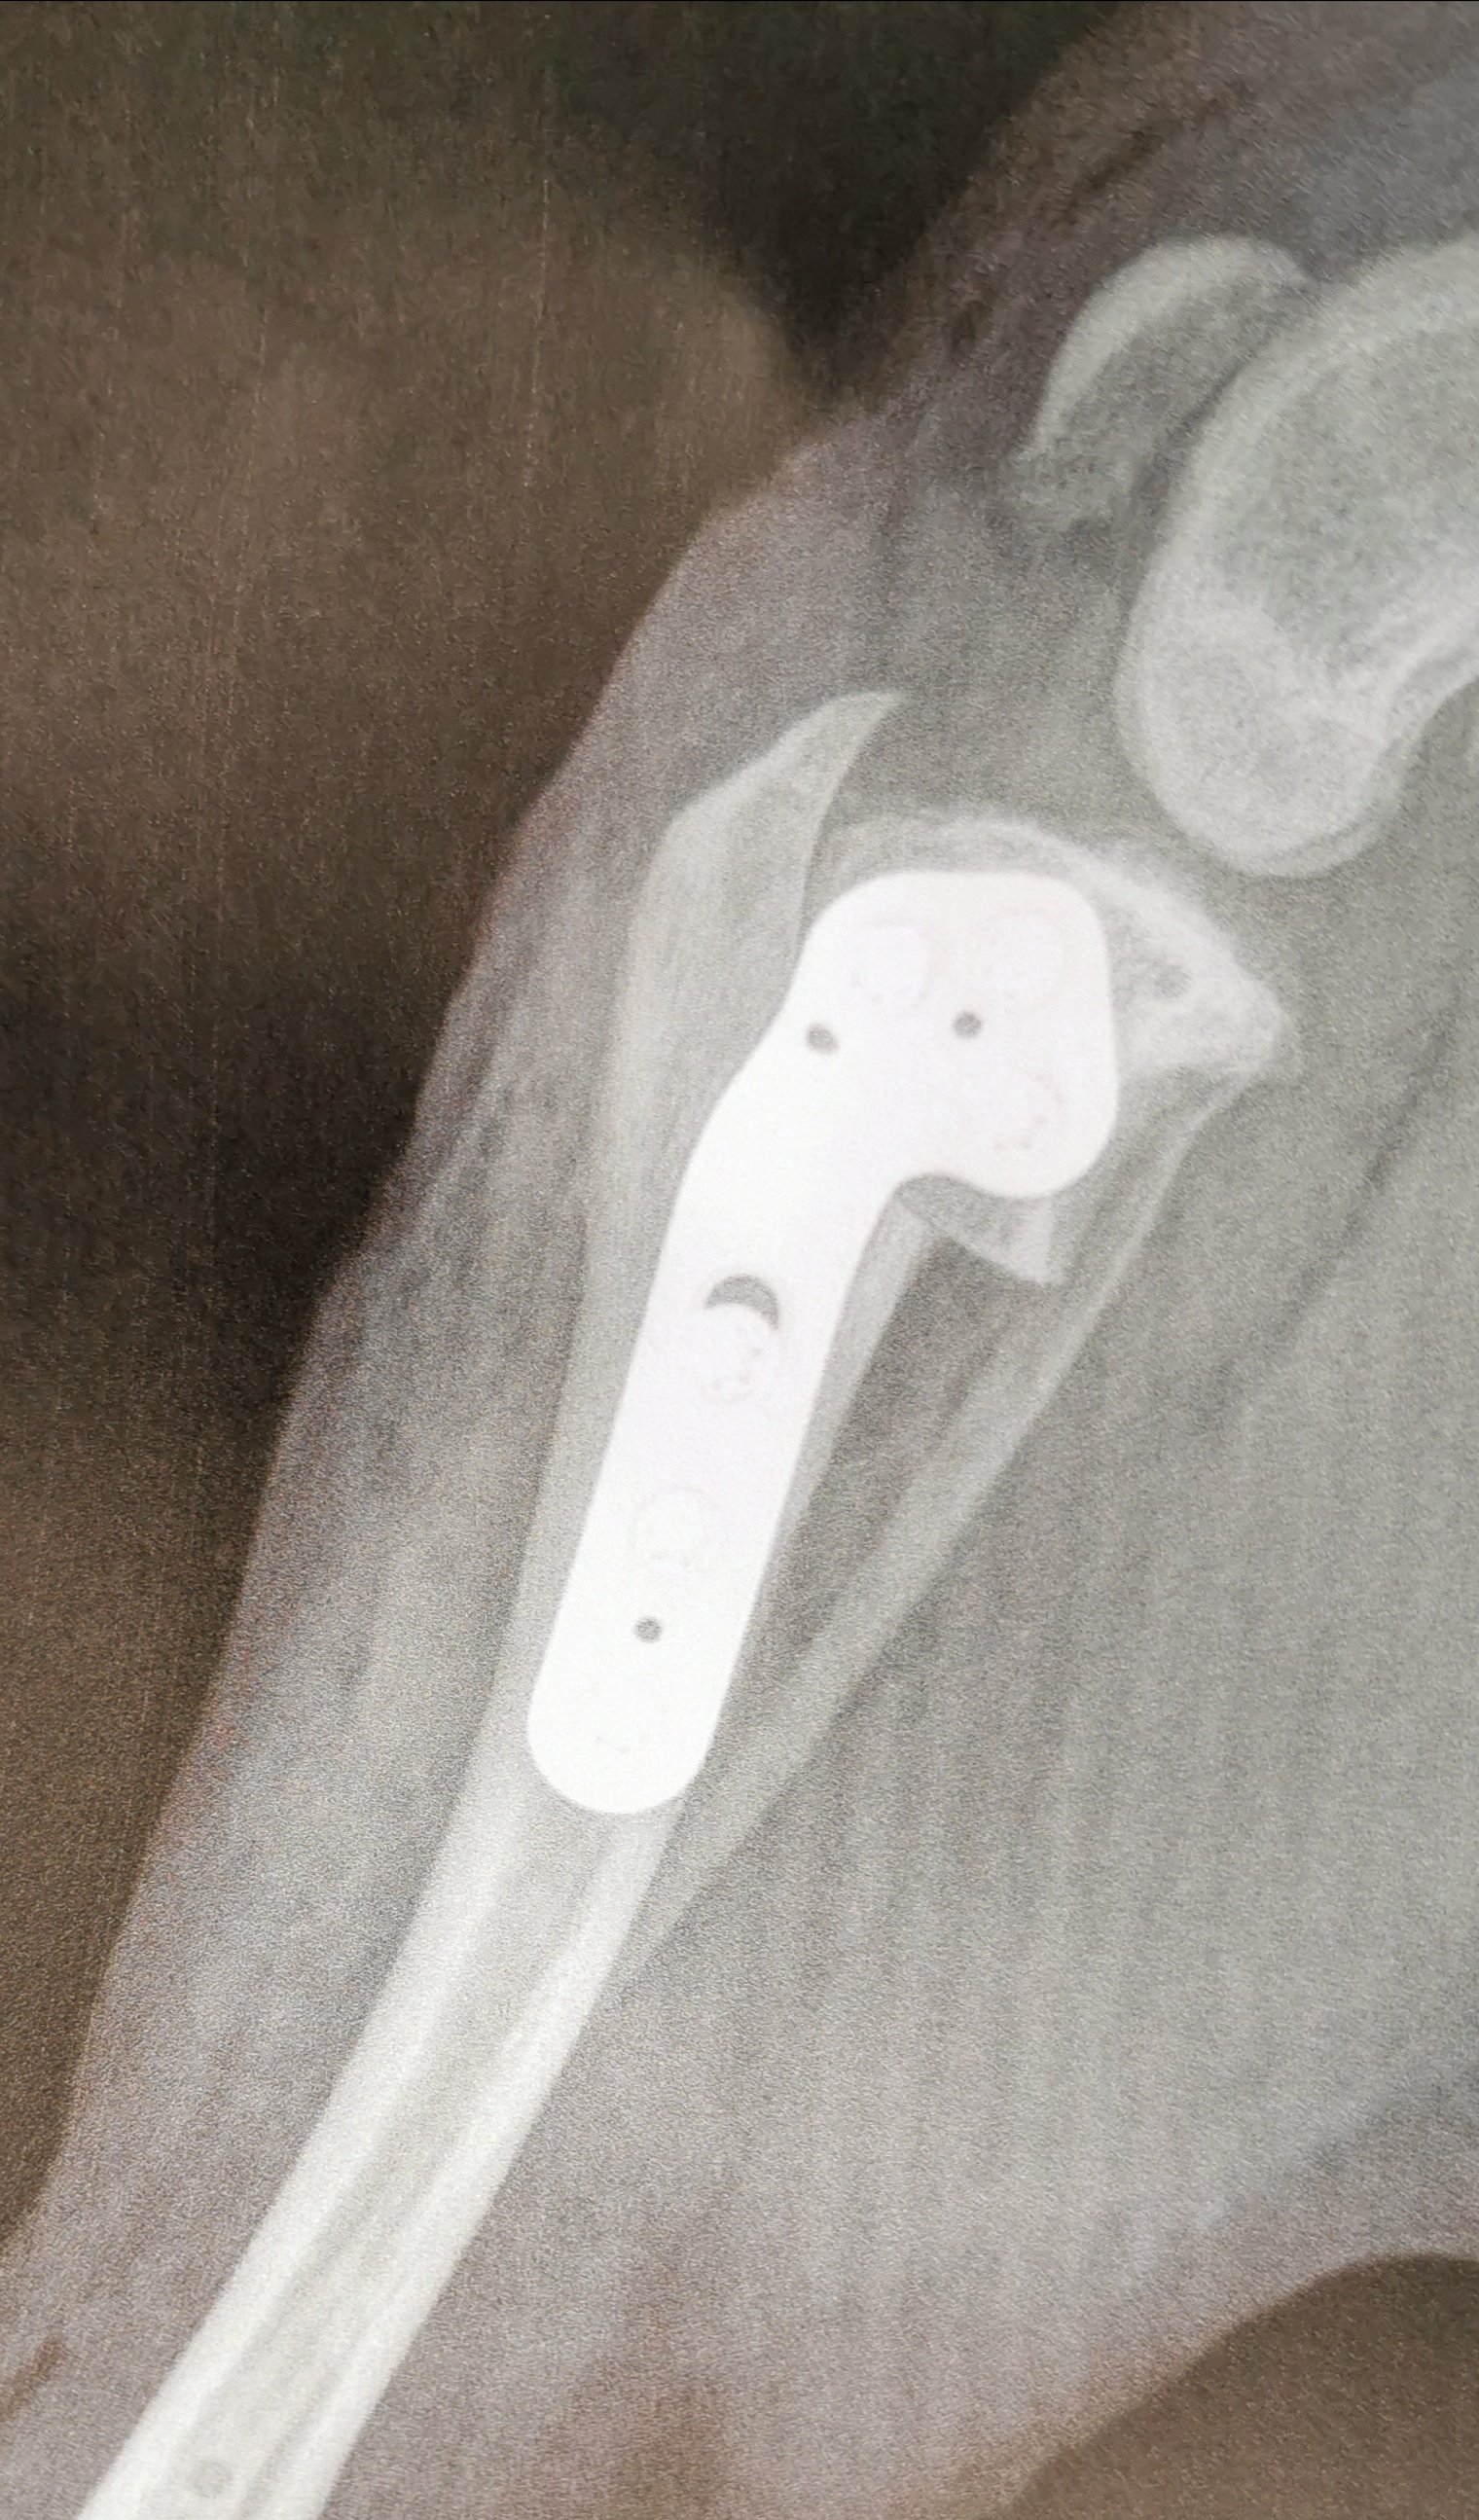

img_20191003_1543242805876165624526290.jpg 03oktober 20193. oktober 20193. oktober 20193. oktober 2019